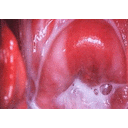

candida-flujo vaginal.jpg

Vaginosis Bacteriana flujo.jpg